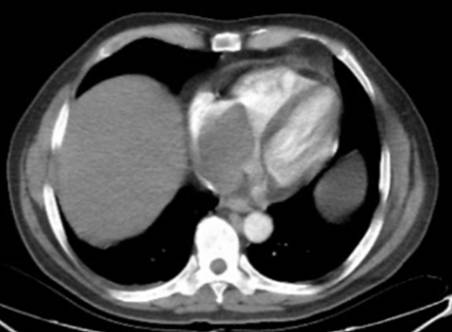

La tomografía simple y contrastada revela trombo tumoral a nivel auricular derecho, con extensión al ostium de la vena renal derecha (figura 1), sin presencia de lesiones metastásica pulmonares, ni hepáticas, sin ectasia de la vía biliar, revela además la presencia de un tumor renal derecho de 15 cm, con 15 UH en fase simple y 59 UH en fase arterial (figuras 2, 3 y 4). El ecocardiograma transesofágico demostró presencia de trombo tumoral en aurícula derecha del 95% de la luz de ésta (figura 5).

Figura 2 Tomografía simple y contrastada que demuestra defecto de llenado a nivel auricular, trombo a nivel de la vena cava inferior, vena renal y tumor renal derecho.

Con los estudios de extensión se establece el diagnóstico de tumor renal derecho cT3c N0 M0, con trombo tumoral Neves IV, así como síndrome de Stauffer. El paciente recibió valoración por medicina interna debido a la hiperglucemia, hiponatremia e hiperazoemia; manejado medicamente con insulina ultrarapida y basal, además con reposición hidroelectrolítica. Se decide someter a tratamiento quirúrgico, el cual consistió en la realización de una nefrectomía radical derecha, resección de trombo de la vena cava inferior a través de venotomía, con abordaje de tipo Chevron y resección intracavitaria de trombo auricular mediante atriotomía a través de esternotomía y by pass cardiopulmonar (figuras 6 y 7). Presentó un sangrado transoperatorio de 2000 ml, requirió trasfusión de 10 concentrados eritrocitarios, 4 plasmas frescos congelados y 4 aféresis plaquetarias, con un tiempo de bomba de circulación extracorpórea de 1 hora y 20 minutos.